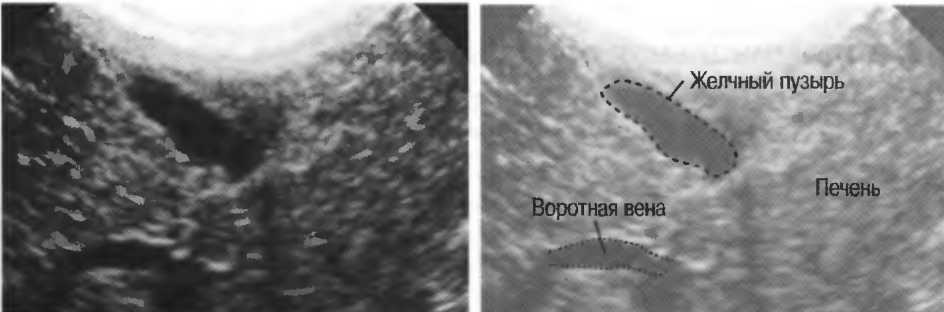

4. У здоровых обследуемых паренхима печени должна быть немного более эхогенна. чем кора рядом расположенной почки (рис. 26).

Рис.26. Продольный срез через печень и правую почку: нормальная паренхима печени более эхогенна, чем паренхима нормальной почки. Это еще один способ проверки качества изображения.